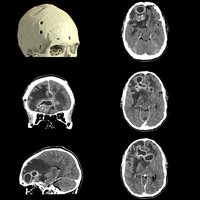

Neben der Qualität der Aufnahmen steht beim Aquilion One PRISM Edition auch die Effizienz im Fokus. So reicht eine einzige Rotation aus, um ein komplettes Herz darzustellen. Dabei wird sowohl die Dosisbelastung reduziert, als auch eine außerordentliche Gleichmäßigkeit der z-Achse garantiert. Die schnelle Bildgebung kommt besonders in der Behandlung von Schlaganfallpatienten zum Tragen, wo jede Sekunde zählt, um Hirngewebe zu retten.

Die Stroke-Evaluation-Plattform von Canon Medical erlaubt die Durchführung einer Perfusionsbildgebung des gesamten Gehirns und eine digitale 4D-Subtraktionsangiographie des intrakraniellen Kreislaufs in nur einer Minute. Mit der Unterstützung durch die 4D-Software wird die Bewertung von Fluss- und Perfusionsfehlern in weniger als fünf Minuten ermöglicht.